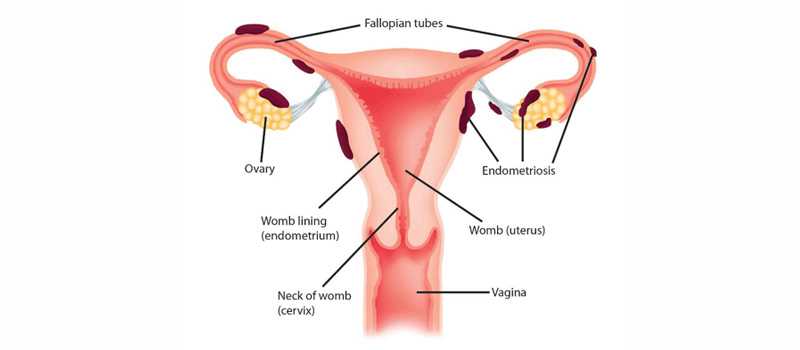

Endometriosis is a condition where the cells that form the lining of the uterus grow into the surrounding areas. Aside from pain, especially during menstruation, during and after intercourse, it can also cause infertility.

About a third of all cases of female infertility are caused by endometriosis where the excess cells occur in the fallopian tubes and block the egg’s passage, or they occur in the ovaries and prevent the release of the egg, or they form in the uterus, ovaries and fallopian tubes and prevent the transfer of the egg to the tube.

Endometriosis is usually treated in one if three ways: watchful waiting, hormone therapy and surgery, depending on your symptoms, age, severity and if fertility is a factor.

The purpose of surgery is to remove as many endometrial implants and cysts as possible, which would relieve pain and improve fertility, and is recommended for women who are still in the child bearing age. It can be done via laparoscopy or laparotomy.

Laparoscopy is the gold standard and preferred method for endometriosis surgery. This is a day care procedure, and you do not need to stay in hospital overnight. Recovery usually takes a 1 -2 weeks.

In a Laparotomy, which is only considered in cases of severe endometriosis, the specialist accesses your reproductive organs through a large incision across your abdomen.

o Endometriosis - a painful condition in which the lining of the uterus grows outside the uterus.